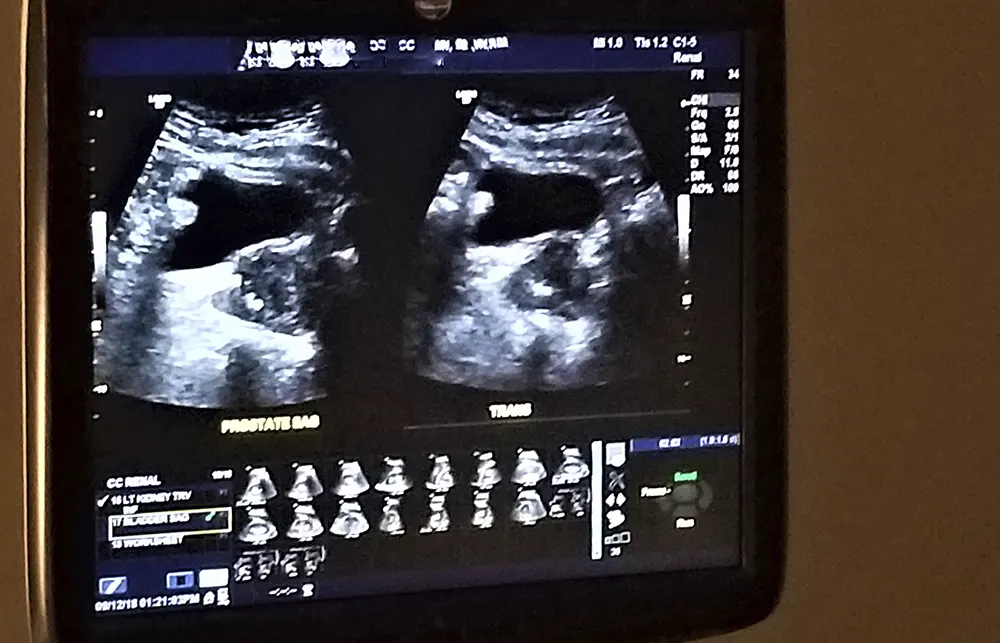

O médico que se especializa em doenças que acometem os rins é o Nefrologista e as condições mais frequentes no seu dia a dia são a Doença Renal Crônica (DRC), Injúria Renal Aguda (IRA), nefrolitíase (cálculo renal/pedra nos rins), hipertensão arterial, doença císticas renais e as glomerulopatias.